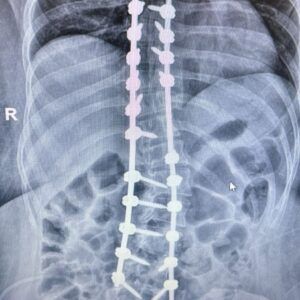

La escoliosis, una alteración en la curvatura de la columna. “Detectarla en etapas tempranas permite evitar su progresión y complicaciones mayores”, señaló.

En paralelo, los avances médicos han transformado las opciones terapéuticas. Procedimientos menos invasivos y tiempos de recuperación más cortos forman parte de la nueva realidad en el tratamiento de estas patologías.

“Hoy podemos ofrecer alternativas más seguras y efectivas, pero cada caso requiere una evaluación individual. No hay soluciones universales”, sostuvo el Dr. Reble.